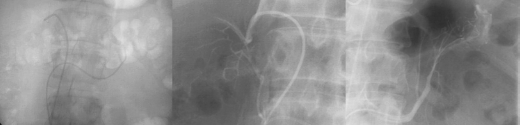

This series of three images reflects a study called “adrenal vein sampling” which requires the simultaneous catheterization of the adrenal veins. This procedure is used to identify relative and absolute concentrations of hormone secretion from the glands to distinguish between normal, bilateral hyperplasia, and unilateral adenoma.

The first image shows the catheters in each of the adrenal veins. The second image is a venogram of the right adrenal vein, and the third a venogram of the left. The venogram is mainly performed to confirm that the catheter is in the correct position, because the veins, particularly the right, may be difficult to find and other small veins coming into the IVC may masquerade as adrenal veins. It is absolutely essential to be in the “right place at the right time” for this test. Courtesy of: Ashley Davidoff, M.D. |

This image is an overlay and an enlarged version of the first image above. It shows the right catheter entering the short right adrenal vein, exiting from above the right gland, and entering the IVC. The left adrenal vein, which is longer, exits from below the left gland and enters into the left renal vein. The insert of the “duel” is a reminder of the short vein on the right and the long vein on the left. Courtesy of: Ashley Davidoff, M.D. |